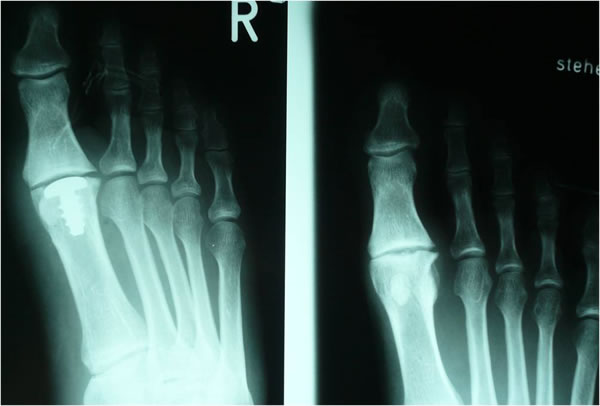

Hallux rigidus

Der Verschleiß bzw. die Zerstörung des Knorpels eines Gelenkes bezeichnet man als Arthrose. Die zunehmende Zerstörung des Gelenkes führt zu einer schmerzhaften Bewegungseinschränkung und zu störenden Knochenanbauten im Bereich des Großzehengrundgelenks. Konflikte im Schuhwerk sind die Folge. Je nach Ausprägungsgrad der Arthrose werden gelenkerhaltende oder eine Versteifungsoperation durchgeführt.

Ein neues Therapiekonzept zur Gelenkerhaltung ist die Implantation einer sogenannten "Hemi Cap" als Oberflächengleitersatz des Mittelfußköpfchens I nach Abtragung der störenden Knochenanbauten bei leichten bis mittelschweren Formen des Hallux rigidus.

Bei schweren Formen des Hallux rigidus macht eine Gelenkerhaltung in der Regel keinen Sinn. Hier kommen gelenkversteifende Operationen oder in Ausnahmenfällen gelenkentfernende Operationen zur Anwendung. Die Gelenkversteifung (Arthrodese) gilt derzeit als "golden standard" bei der operativen Behandlung von schweren Formen des Hallux rigidus.